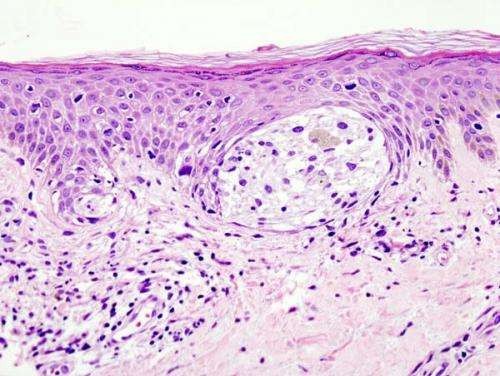

Hình ảnh khối ung thư sinh thiết dưới da.